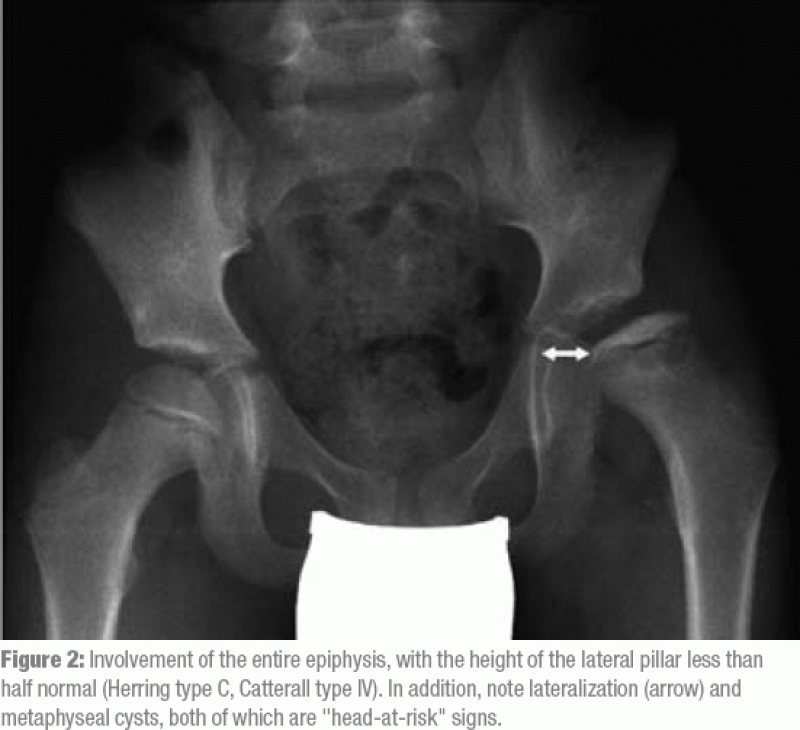

Legg Calve Perthes Disease Radiology / Perthes Disease Symptoms Risk Factors And Complications - Mri may be required for diagnosis of occult or early disease.